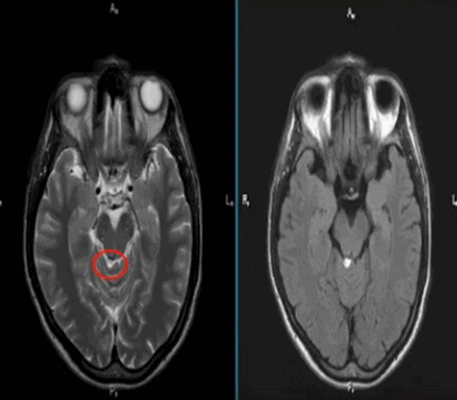

Липома четверохолмной цистерны на МРТ (обведена кругом)

МРТ назначают, если у пациента наблюдаются неврологические отклонения, обусловленные поражением мозговой ткани. Симптомами могут быть: